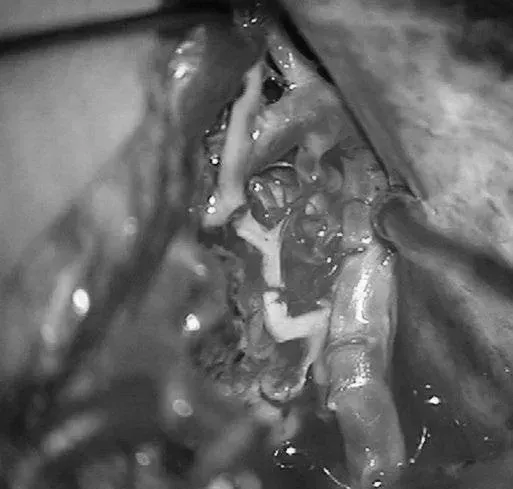

▼移除AVM

▼显露PCA周围至其ParOccA和CalcA(P2P)分叉